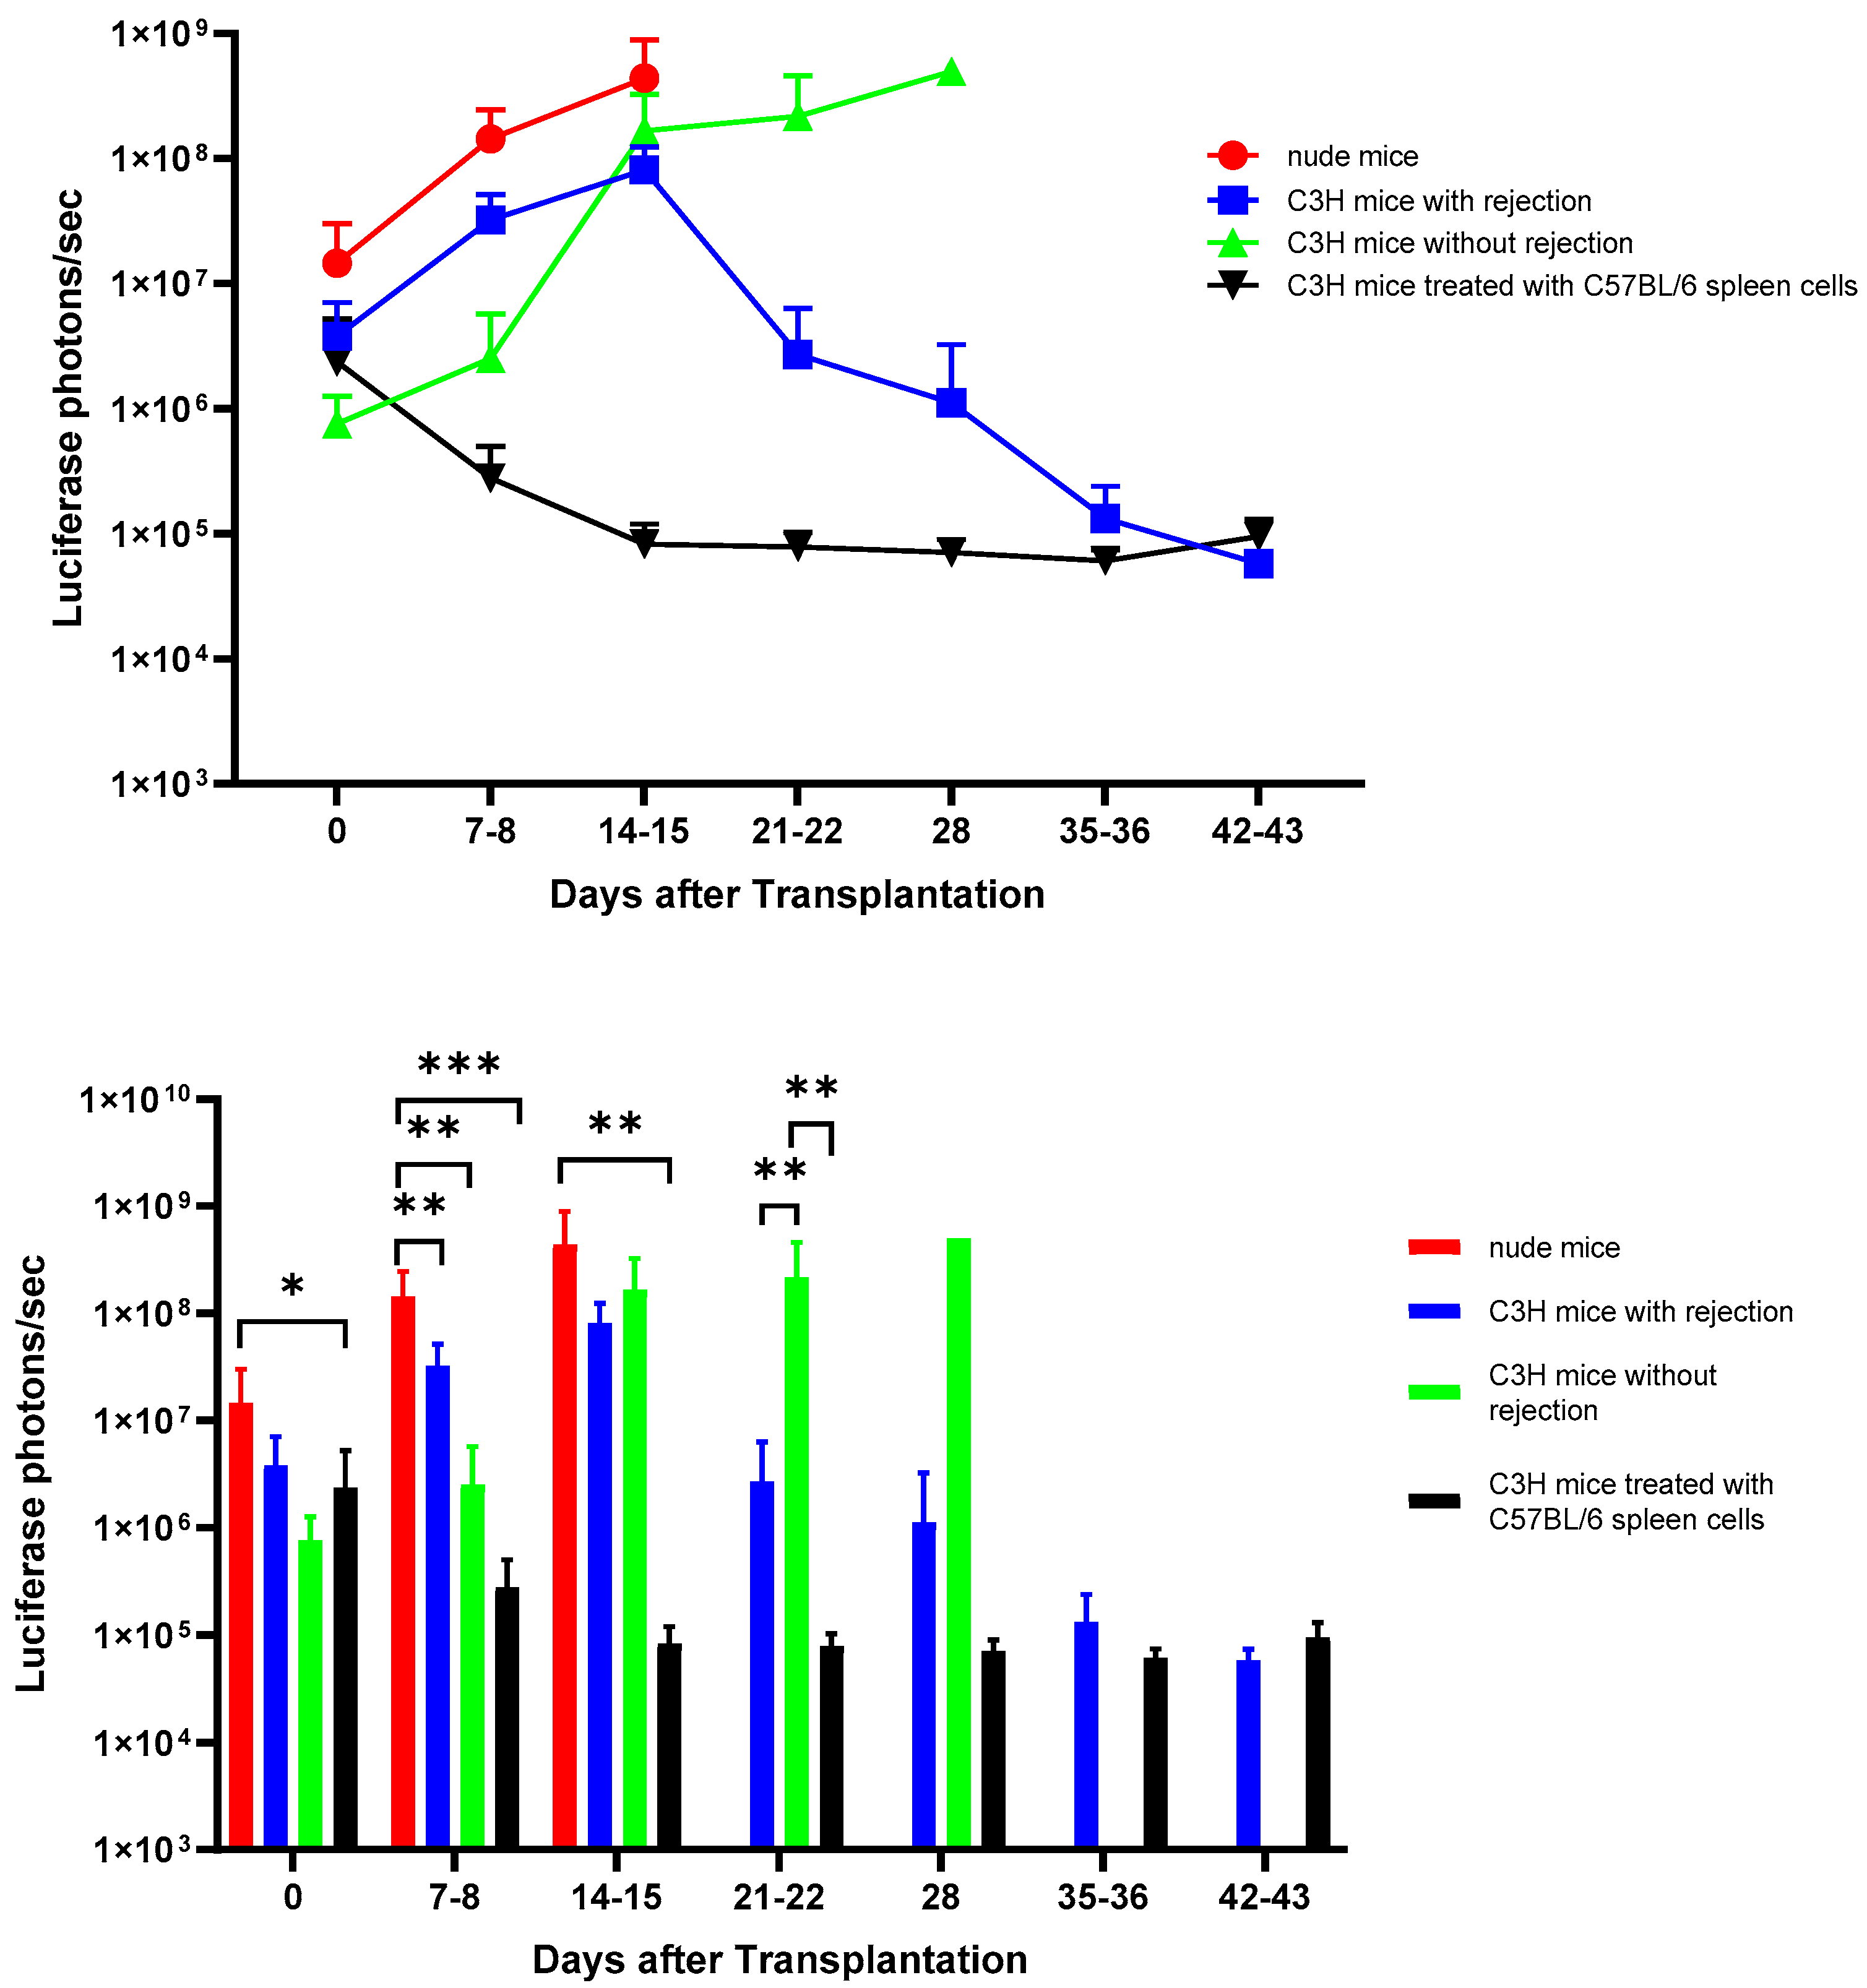

3.2. In Vivo Bioluminescence Imaging of Matrigel-Embedded MIN6 Cells Subcutaneously Transplanted in Nude and C3H Mice